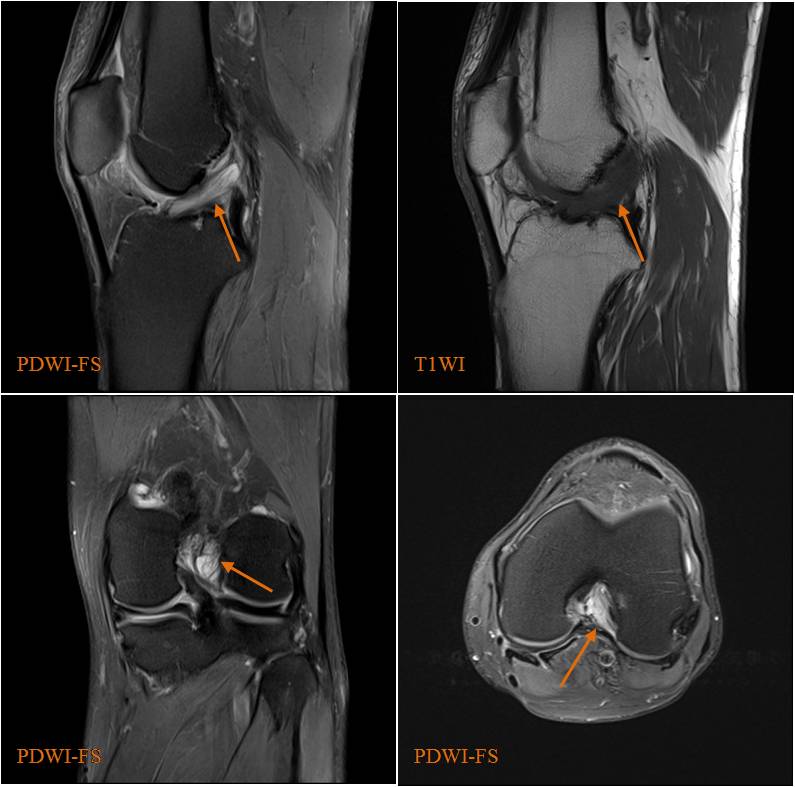

圖1 前交叉韌帶黏液樣變性

男,53歲,左膝關(guān)節(jié)疼痛不適半年余,外傷史(-)。MRI,前交叉韌帶彌漫性增粗,信號增高(PDWI-FS,橙箭),纖維束分離、尚連續(xù)完整,呈“芹菜梗”樣表現(xiàn)。